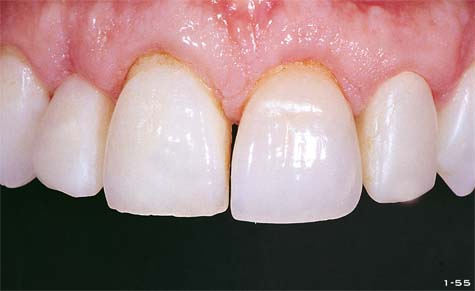

Abb. 1-55 Klinisches Foto der Oberflächencharakteristika der natürlichen Zähne. Der schwarze Hintergrund erleichtert dem Techniker die Arbeit beim Aufschichten der Keramik.

Abb. 1-56a und 1-56b Die seitlichen Schneidezähne sind gebleicht und mit Fiberglasstiftaufbauten versorgt. Die Gingiva kehrt nach der Resektion kontinuierlich in ihre Position zurück.